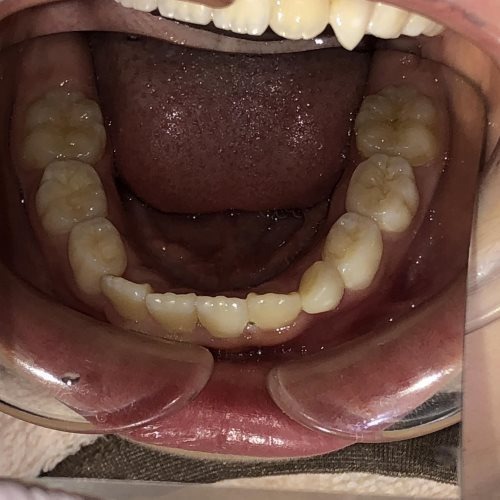

• BEFORE

症例集 インビザライン 下顎

AFTER